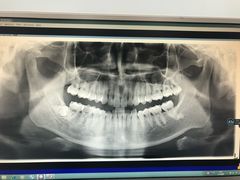

• 德伦口腔

• -德伦口腔

Misery | 17-12-08

报错